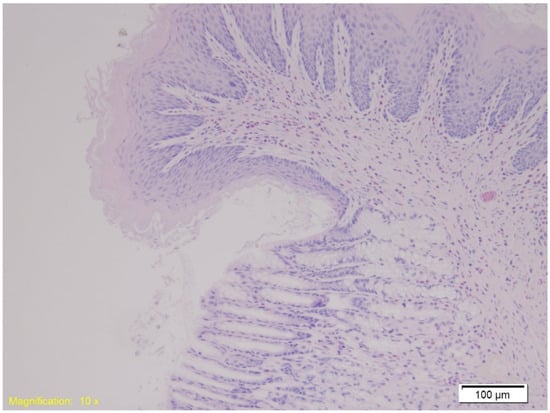

- Cytokeratin 7 (CK7) (rabbit monoclonal, 1:100)—Gastroesophageal Junction: CK7 is an intermediate filament protein expressed in epithelial cells, particularly in glandular and transitional zones. Its expression helps assess epithelial integrity and stress responses in hypothermia-related gastrointestinal injury.

- Cytokeratin 20 (CK20) (mouse monoclonal, 1:150)—Gastroesophageal Junction: CK20 complements CK7 in characterizing epithelial differentiation and stress. Its expression pattern can help distinguish hypothermia-induced epithelial changes from other causes of mucosal injury.

| Gastro-esophagus | Muscle layer hypertrophy, congestion, marked subepithelial eosinophilia. | Similar findings as Group K. | Similar findings as Group K. |